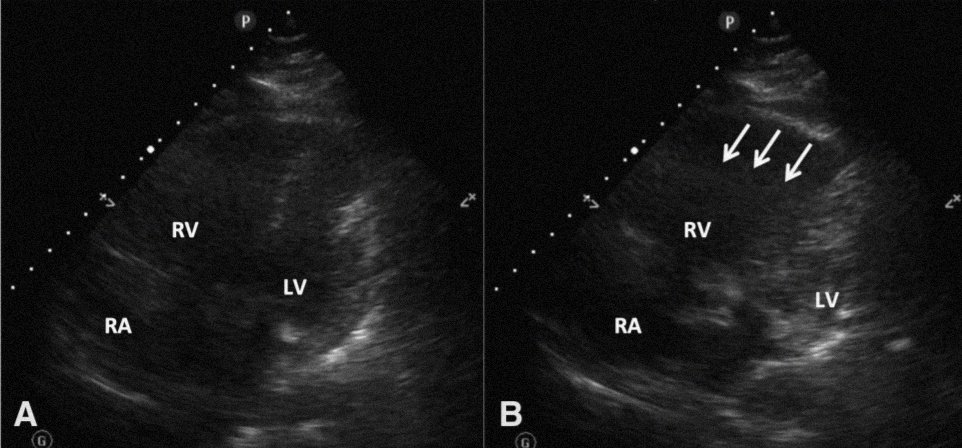

Beautiful capture of McConell's sign: RV free wall akinesia with sparing of apex.

Originally described in 1996 by McConnell et al. as akinesis of mid-RV free wall with normal apical contraction, he and his team found a sensitivity of 70% and specificity of 94% for PE in their validation cohort.